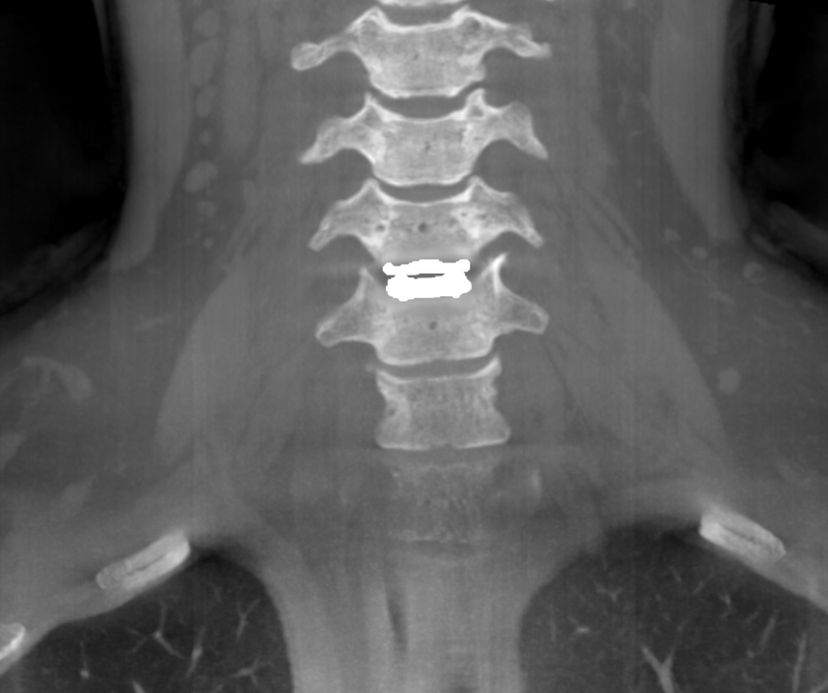

See Factor CT3™ is an imaging diagnostic device that integrates: High Resolution Computed Tomography

High Definition Volumetric Imaging (HRCT) technology, Digital Radiography (DR) and Fluoroscopy (FL) into one device.

Predictive + Preventative Imaging: SFCT3 delivers 0.1 voxel precision, true volumetric 3D imaging (no interpolation), catching things even MRIs miss.

100% Real Data: No interpolation. Just pure, gapless image data with extraordinary isotropic resolution down to 0.2mm offering precise insight into both soft and hard tissues.